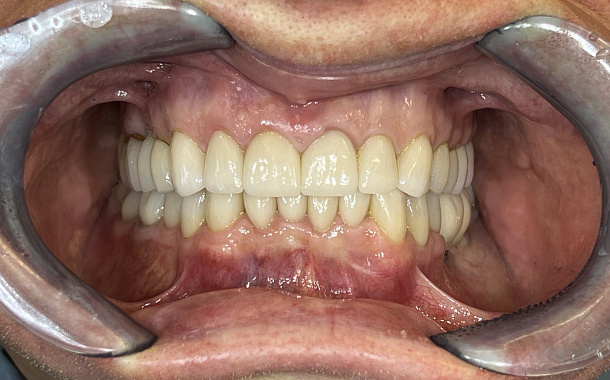

- Установка временной ортопедической конструкции.

Одномоментное удаление и установка зубного импланта в лунку помогают сократить до минимума костно-пластические и мягкотканные манипуляции, сохранить анатомию гребня альвеолярного отростка и сформировать естественный профиль прорезывания искусственной коронки, то есть создать иллюзию своего зуба.

Благодаря временным коронкам высота прикуса и работа сустава остаются правильными с первого дня начала имплантации. Постоянные коронки фиксируются только спустя 4–6 месяцев, когда зубной имплант полностью прижился.